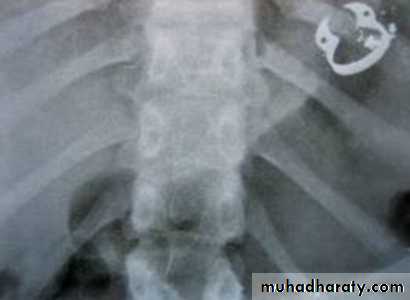

Severe swelling caused by injecting hydrogen peroxide irrigant into tissues.